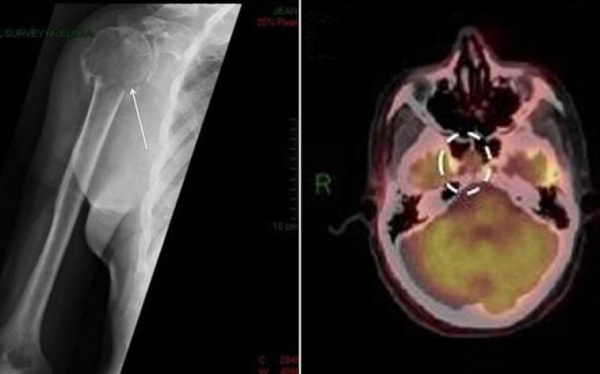

Больной Г., 44 года, обратился в клинику с жалобами на общую слабость, наличие опухолевого образования в желудке. Из анамнеза известно, что с октября 2015 г. у него появились нарастающая слабость, головокружение, несколько раз наблюдалась мелена. При обследовании по месту жительства диагностирована анемия (гемоглобин 90 г/л), в связи с чем госпитализирован в одну из городских больниц Москвы, где проведено ЭГДС, при которой выявлено образование в желудке. Проведена гемостатическая и противоязвенная терапия с кратковременным улучшением. Пациент был выписан. В дальнейшем его самочувствие стало вновь ухудшаться, за 2 мес отмечено 6 эпизодов желудочного кровотечения, и в тяжелом состоянии больной вновь был госпитализирован. При повторном обследовании выполнена биопсия образования желудка. При гистологическом исследовании высказано предположение о диффузной В-клеточной крупноклеточной лимфоме. Начата противоопухолевая терапия интенсивными курсами по программе R-DA-EPOCH. Выполнено 2 курса без существенного эффекта (рис. 1). Рис. 1. Компьютерная томограмма брюшной полости. Неравномерное утолщение стенки средней трети тела желудка по большой кривизне. Произведена интенсификация лечения с применением программы DHAP в количестве 2 курсов. При обследовании по данным компьютерной томографии (КТ) и впоследствии позитронной эмиссионной томографии (ПЭТ) и КТ в стенке желудка по большой кривизне выявлен участок размером 40×16 мм, с выраженным повышением накопления РФП SUV-6, 12, других очагов патологической метаболической активности не обнаружено (рис. 1, 2). Рис. 2. ПЭТ (а) и КТ (б). Повышенное накопление РФП в стенке средней трети желудка по большой кривизне (SUV-6, 12).

- Рентгенодиагностика. При костных болях назначается рентгенография грудной клетки, позвоночника и конечностей, с помощью которой определяются объемные новообразования. Для точной визуализации опухолей и определения степени распространенности процесса проводится КТ пораженной области тела. Методика ПЭТ-КТ показана для диагностики генерализованной плазмоцитомы.